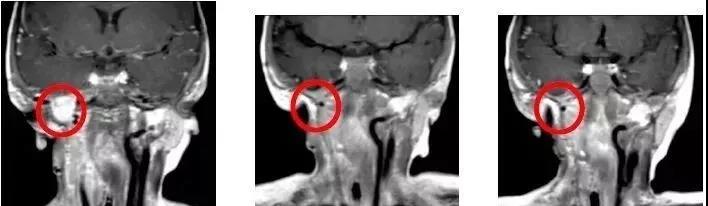

儿童纤维肉瘤: 一个16个月大的婴儿 治疗前:基因检测后发现ETV6-NTRK3突变。经过3次手术和化疗,效果仍不明显。治疗后:磁共振显示成人剂量的抗癌药物维特拉克维治疗3个周期后,肿瘤体积减少了90%。